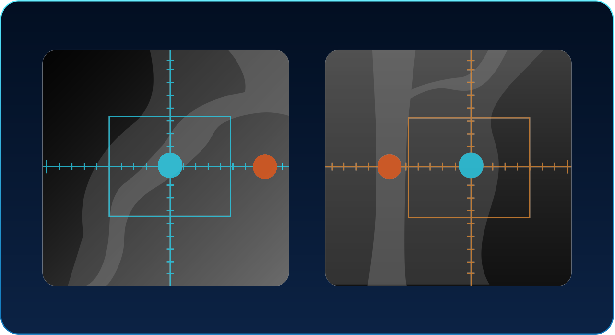

Accu-Positioning

A deep learning-driven automated positioning technology based on 3D camera, which identify anatomical points through sensors, generation 3D image information and automatically locating the position.

Accu-ISO

By utilizing a 3D camera and advanced technology, the system is able to identify the exact center of the scanning area with pinpoint accuracy, aligning it with the target under just one-click.